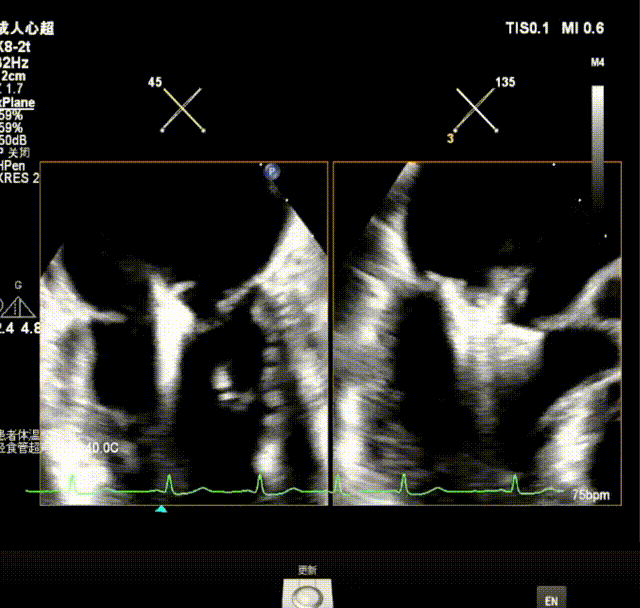

瓣上M/L和A/P调整瓣膜夹,在X-plane进行超声确认(视频),进行弹道路径检查;

3D指示下调整瓣膜夹朝向病变区域